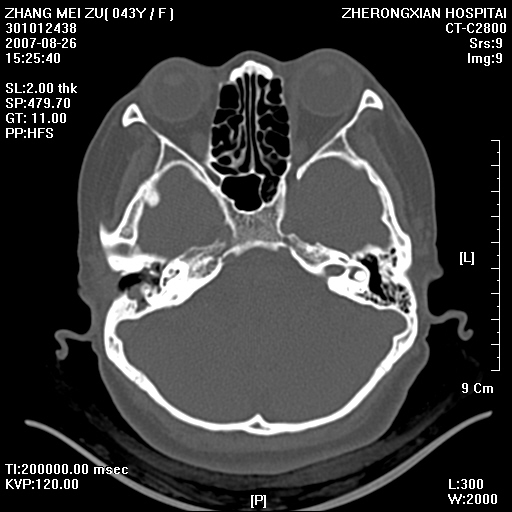

标题: CT9512:F43Y,是肉芽肿还是胆脂瘤?诊断报告该如何出? [打印本页]

标题: CT9512:F43Y,是肉芽肿还是胆脂瘤?诊断报告该如何出?

右耳硬化性乳突炎并胆脂瘤形成

右耳硬化性乳突炎并鼓窦入口胆脂瘤形成,左侧乳突炎

右侧中耳乳突炎,伴鼓窦入口胆脂瘤形成.

从发病部位及骨质破坏应该考虑是获得性胆脂瘤

典型胆脂瘤,从上鼓室,乳突窦入口到乳突窦有明显光滑的骨质破坏和软组织结节均为胆脂瘤特点.而肉芽肿对骨质的破坏是轻微的.值得关注的是乳突后壁被破坏只剩薄薄的一层,如果再不尽快治疗,胆脂瘤如果突破其后壁即可能形成耳源性脑脓肿了.